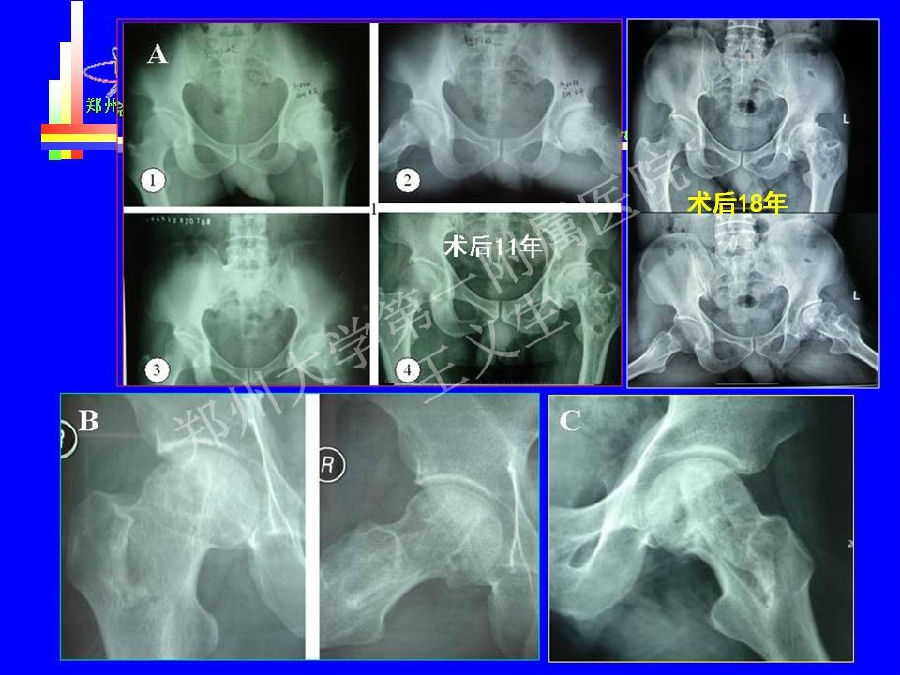

2014-04-24 文章来源:郑州大学第一附属医院骨科 王义生 我要说